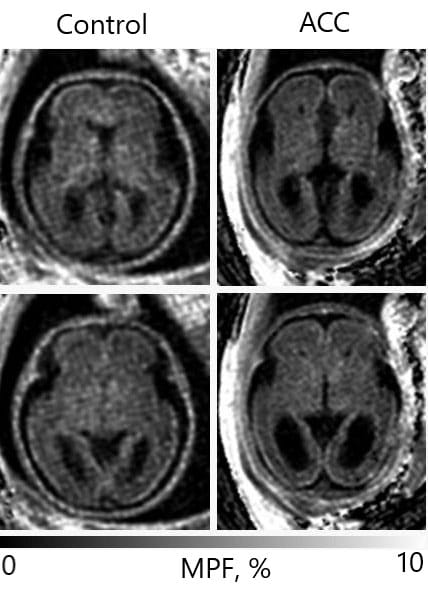

Данная методика уже апробирована авторами на плодах гестационного возраста более 20 недель. Эти исследования показали, что методика МПФ действительно позволяет в короткие сроки (менее 5 минут) оценить очень малые количества миелина. Также исследователям удалось проследить этапы развития и распределения миелина в мозге плода (рис.1).

распределения миелина у плода в норме (Control) и с агенезией мозолистого

тела (ACC). (Изображение предоставлено МТЦ СО РАН).